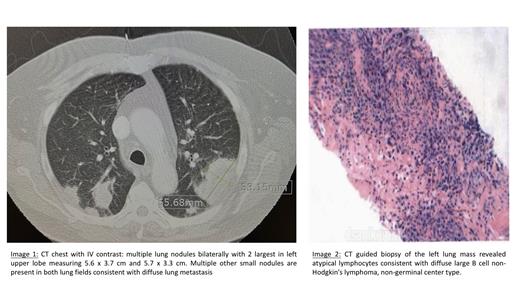

Upon presentation, work up showed mild anemia (Hb 11.1 g/dL). Cardiac work up for chest pain was unremarkable. Chest X-Ray revealed mass like opacities in each lung with largest in left mid lung measuring up to 6 cm. CT chest with IV contrast revealed multiple lung nodules bilaterally with 2 largest in left upper lobe measuring 5.6 x 3.7 cm and 5.7 x 3.3 cm. Multiple other small nodules are present in both lung fields consistent with diffuse lung metastasis. No lymphadenopathy was noted. (Image 1) PET CT scan was significant for bilateral FDG avid lung lesions. No evidence of other FDG avid disease.